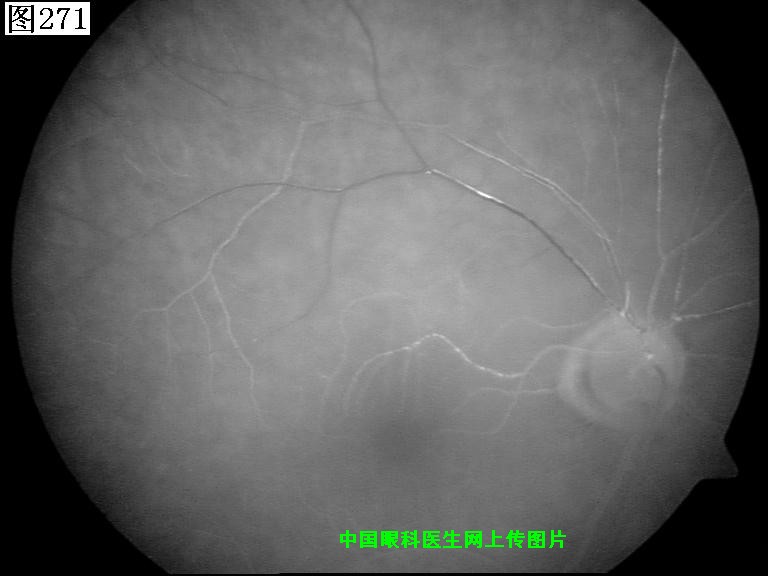

269 270 271 272